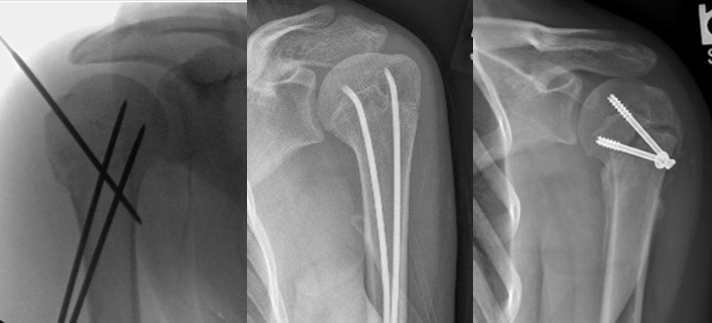

六,手术治疗:

-

经皮穿针固定

弹性髓内钉固定

空心螺钉固定

钢板内固定

固定方式选择

目前尚无公认的最佳固定策略

建议根据具体病例情况个体化选择固定方式

需综合考虑患者年龄、性别、骨折移位程度及骨骼重塑潜力等因素